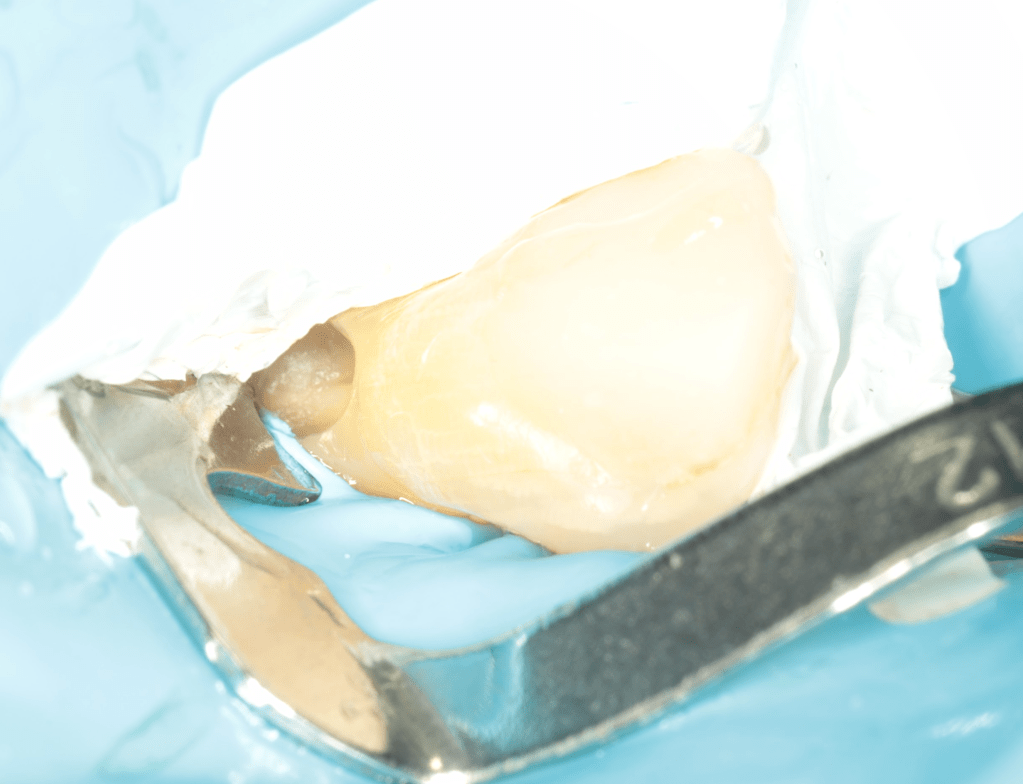

REIMPLANTES

Intencional por dificil acceso coronal y quirúrgico

Reinplante por fracaso de tratamiento

Reimplante, istmo apical, curación cortical palatina 1 año